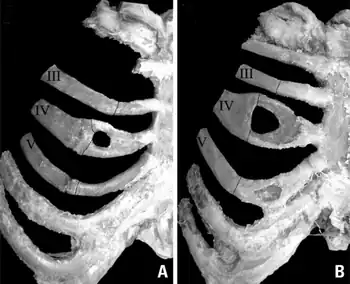

Bifid rib

A bifid rib is a congenital abnormality of the rib cage and associated muscles and nerves which occurs in about 1.2% of humans. Bifid ribs occur in up to 8.4% of Samoans.[1] The sternal end of the rib is cleaved into two. It is usually unilateral.